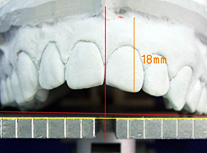

上顎前歯部(口腔前庭口~切縁間距離)平均22mm 18mm (平均より4mm短い)(写真A) |

上顎前歯部(口腔前庭口~切縁間距離)平均22mm 18.5mm (平均より3.5mm短い)(写真A) |